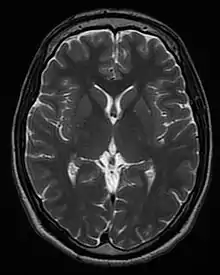

| T2 weighted | T2 | Measuring spin–spin relaxation by using long TR and TE times |

Standard foundation and comparison for other sequences |